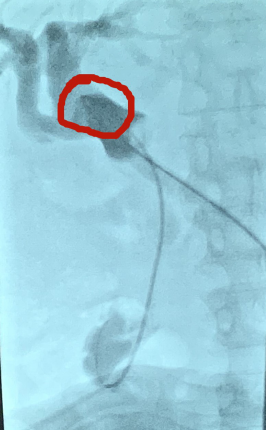

T管近端与胆总管下段方向形成近360°夹角

术中,肿瘤科手术团队在DSA引导下,不开任何切口,经留置T管开展手术。由于T管近端与胆总管下段方向形成近360°夹角(正常为经皮直接穿入),位置“刁钻”,并且胆总管上段、下段形成2处狭窄,为手术实施带来了重重险阻!